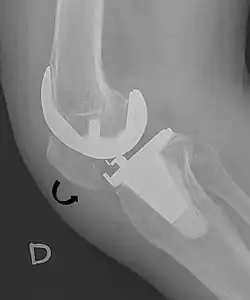

For recurrent patellar dislocations or cases with chronic instability, surgical intervention may be necessary. Patella stabilization surgery aims to restore proper kneecap tracking and reduce the risk of future dislocations.[4] Surgical options include reconstruction of the medial patellofemoral ligament (MPFL), realignment procedures such as osteotomy, and soft tissue adjustments around the patella.[4] MPFL reconstruction typically involves harvesting a hamstring tendon, commonly the gracilis, to create a new ligament that is positioned anatomically and secured with suture anchors.[4]

The Insall-Salvati ratio helps to indicate patella baja on lateral X-rays, and is calculated as the patellar tendon length divided by the patellar bone length. An Insall-Salvati ratio of < 0.8 indicates patella baja.[7]

- ^ a b Douglas Dennis (2017-02-25). "TKA in Patella Baja (Infera)". Orthobullets. Retrieved 2019-02-08.